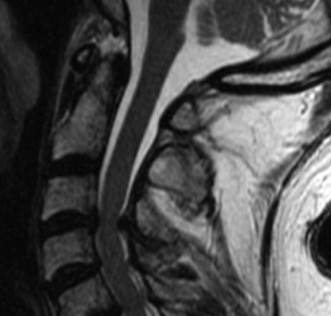

CASE 1 A 63-year-old male sustained a hyperextension injury to his neck while diving into a pool. Upon presentation, he reports decreased sensation in his hands and decreased strength in his arms and wrists, but no lower extremity complaints. On motor examination, he has 5/5 strength in his deltoids and elbow flexors and 4/5 strength in the elbow extensors, wrist extensors, and finger flexors. Lower extremity motor examination is normal. Sensation is decreased to light touch in both hands. Otherwise his sensation is preserved. Images of his cervical spine are shown in Figures 1–1 to 1–3.

Figure 1–2

The correct answer is (B). The clinical scenario describes a patient with central cord syndrome (CCS). CCS continues to be the most common incomplete spinal cord injury accounting for 15.7% to 25% of all spinal cord injuries. The characteristic presentation is an extension moment injury in a previously spondylotic and stenotic spine. Figures 1–1 to 1–3 demonstrate a spondylotic spine with central narrowing and CSF effacement that is worst at the C3–4 level. Bleeding, edema, and/or Wallerian degeneration lead to damage of the lateral corticospinal tract which is the main descending motor tract in the spinal cord. The more central anatomic position of the homunculus to the upper extremities places them at greater risk than those to the lower extremities. As such, injury to the lateral corticospinal tract is characterized by upper more than lower extremity involvement and motor deficits being more pronounced than sensory deficits.